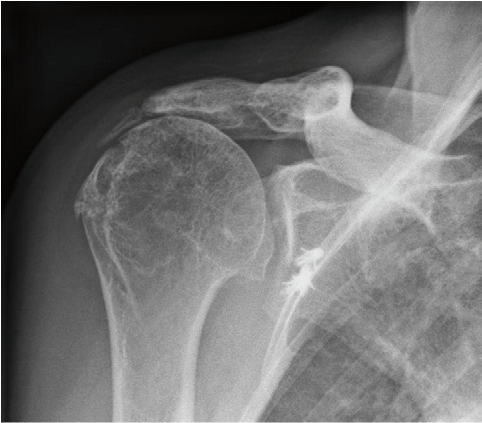

Anatomische Schultergelenkendoprothese

Die anatomische Schultergelenkendoprothese ersetzt den Oberarmkopf (Humeruskopf) und die Schultergelenkspfanne (Glenoid). Sie kommt vor allem dann zum Einsatz, wenn die Sehnen der Schulter (Rotatorenmanschette) noch intakt, aber beide Gelenkpartner verschlissen sind. Die Rotatorenmanschette ist der "Motor" für den Oberarm, so dass postoperativ eine gute Schulterfunktion bei langer Lebensdauer der Prothese zu erwarten ist.

Das Fallbeispiel zeigt ein Röntgenbild mit Arthrose von Kopf und Pfanne mit aufgebrauchtem Gelenkspalt und ein postoperatives Röntgenbild nach 3 Jahren mit eingebrachter TEP (Kopf und Pfanne wurden ersetzt). Da die Gelenkpfanne aus Polyethylen ist, kann man sie auf dem Röntgenbild nicht so genau sehen wie die Kopfprothese.